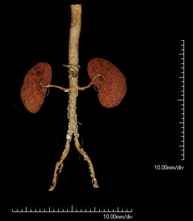

- Angio-TC arterias renales

Prueba diagnóstica no invasiva que consiste en el estudio de las arterias renales obteniendo imágenes de alta definición anatómica mediante el empleo de un equipo de TC (Tomografía Computarizada) y de contraste yodado. La calidad de las imágenes permite realizar reconstrucciones en 2D y 3D gracias a estaciones de trabajo especializadas en el estudio arterial. Esta prueba está indicada, por ejemplo, en aquellos pacientes que sufren de HTA refractaria al tratamiento, en pacientes con lesiones renales para tener un mapa "vascular" pre-quirúrgico, etc.